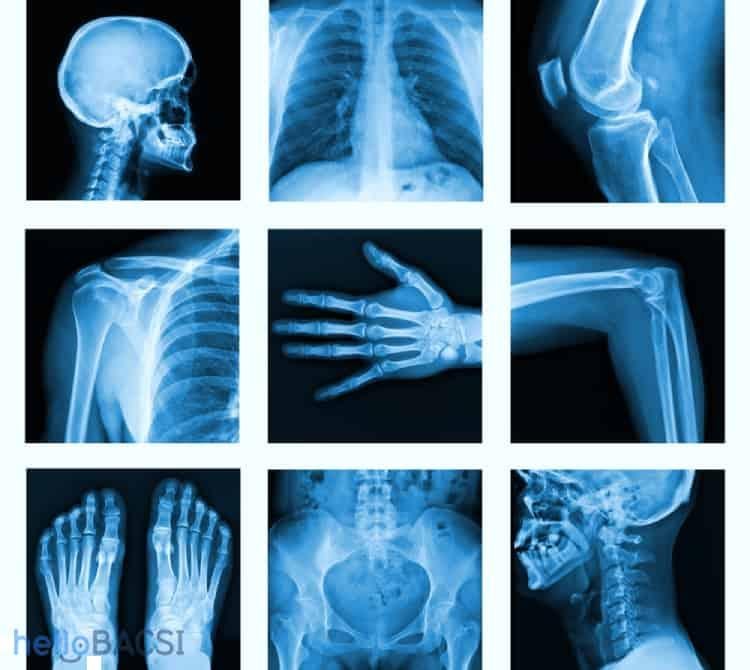

Chụp X-quang là một xét nghiệm hình ảnh nhanh chóng, không gây cảm giác đau, giúp nhìn thấy hình ảnh các cấu trúc bên trong cơ thể bạn, đặc biệt là khung xương.

Bác sĩ có thể chỉ định bạn đi chụp X quang để kiểm tra nhiều bộ phận của cơ thể nhằm giúp chẩn đoán hay xác nhận tình trạng sức khỏe, chẳng hạn như:

- Chụp X quang ngực cho thấy tình trạng phổi, dấu hiệu nhiễm trùng, phì đại cơ tim hoặc khối u ở ngực

- Chụp X quang xương để phát hiện gãy xương, loãng xương, nhiễm trùng hoặc khối u

- Chụp X quang vú quan sát sự thay đổi trong mô vú như khối u, ung thư vú

- X quang nha khoa đánh giá răng và hàm

- X quang hệ tiêu hóa giúp phát hiện tắc ruột, hóc dị vật

- Sàng lọc tia X theo thời gian thực (soi huỳnh quang) giúp các bác sĩ đặt ống đỡ động mạch hoặc kiểm tra vị trí của dây dẫn; hoặc chụp động mạch; hoặc để hiển thị đường nét cấu trúc của cơ thể (X quang có thuốc cản quang)

- Chụp cắt lớp vi tính CT cũng là một dạng chụp X-quang, gồm một loạt các tia X chiếu vào một khu vực trên cơ thể để tạo ra hình ảnh 3 chiều (3D).